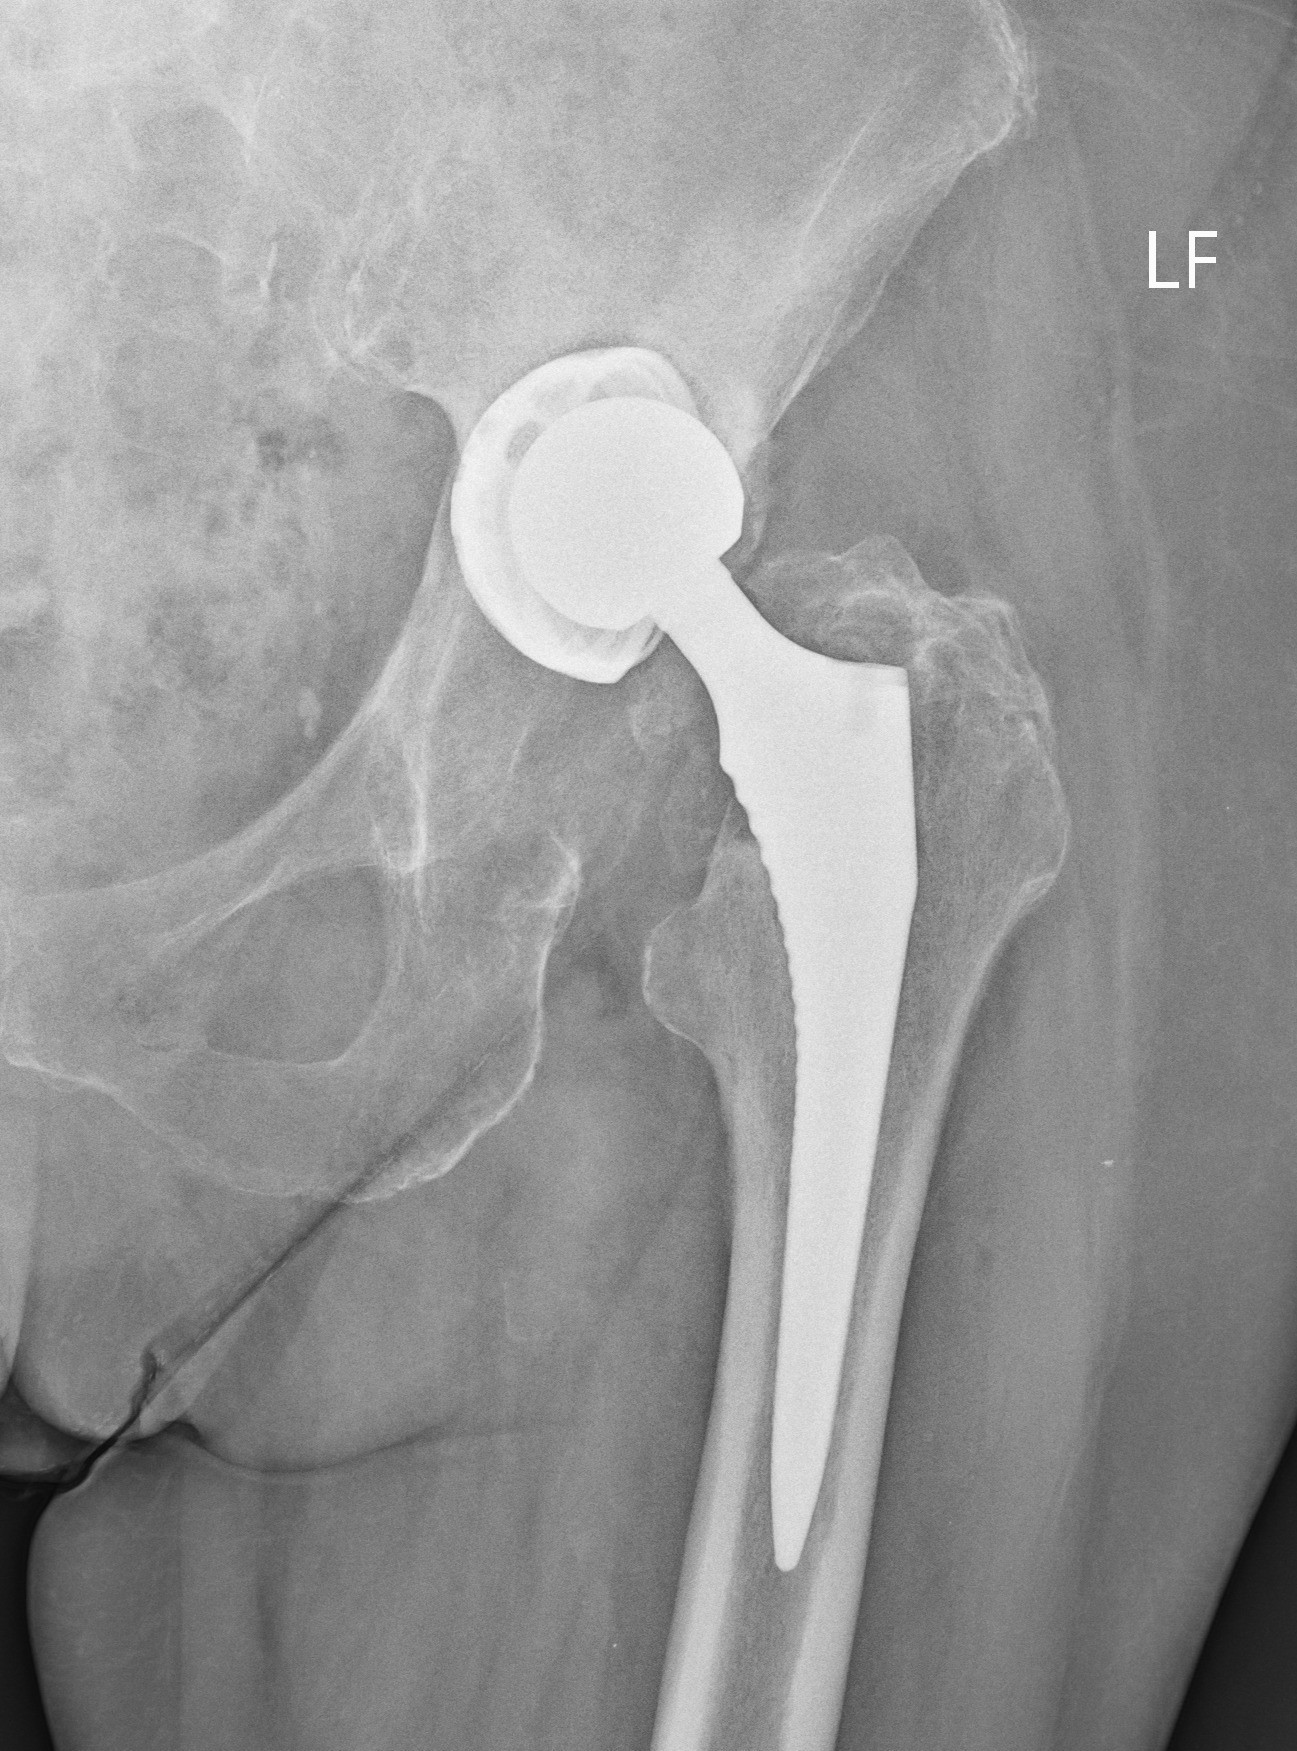

Zdroj: UNB

Kĺb pred operáciou